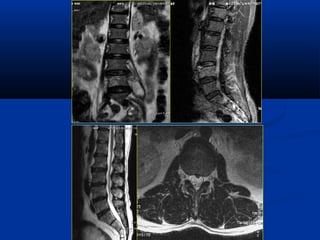

Diffusion Perfusion

Diffusion Tensor MRI

(DTMRI)

Choline vaø lactic acidPHOÅ COÄNG HÖÔÛNG

TÖØ

(SPECTROSCOPY/MRS)